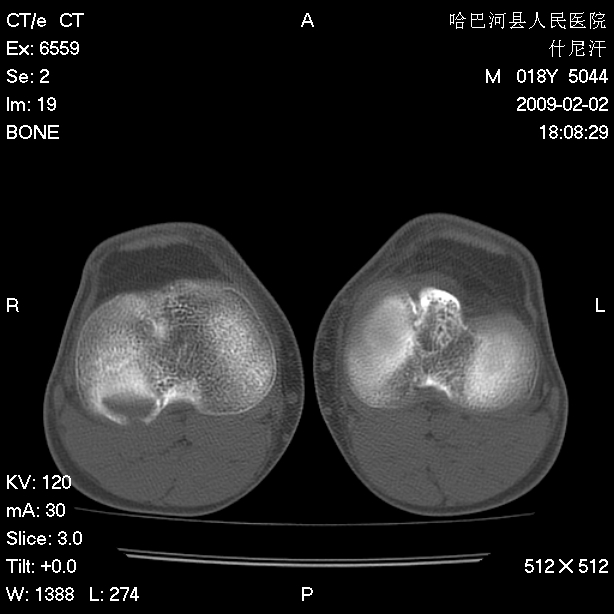

标题: CT17889:外伤后右膝关节反复疼痛3年余 [打印本页]

标题: CT17889:外伤后右膝关节反复疼痛3年余

ct未见明显异常。关节腔未见明显积液,半月板未见明显撕裂。但最好还是mri看看韧带及半月板情况。